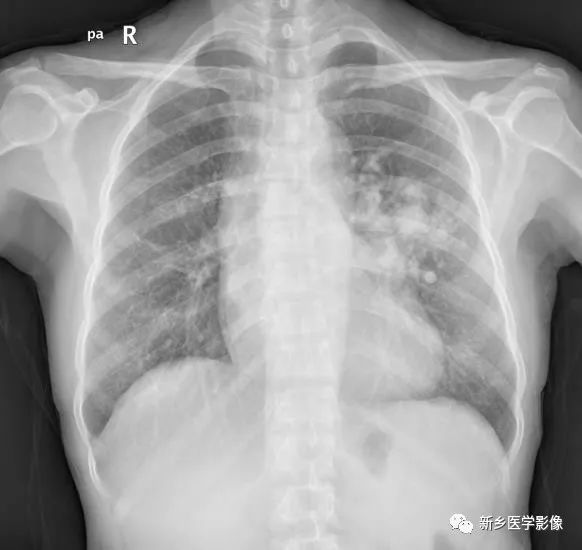

【病例】肺动脉静脉畸形1例CT

女,49岁

主诉: 间断发热1年余,再发4天。现病史:1年前受凉后出现发热,最高体温至37.8-38℃,多于午后出现。4天前感冒后再次出现发热,午后出现,热峰至38℃,伴双腿膝关节酸沉、乏力。

既往史:自诉有“先天性心脏病”30余年,当地医院诊断为“二尖瓣狭窄”,未给予诊治。诉“低血压”史,具体血压值不详。

查体:杵状指(趾)

X线胸片:表现为肺外带类圆形结节影,部分病灶边缘可见指向肺门的增粗血管影。